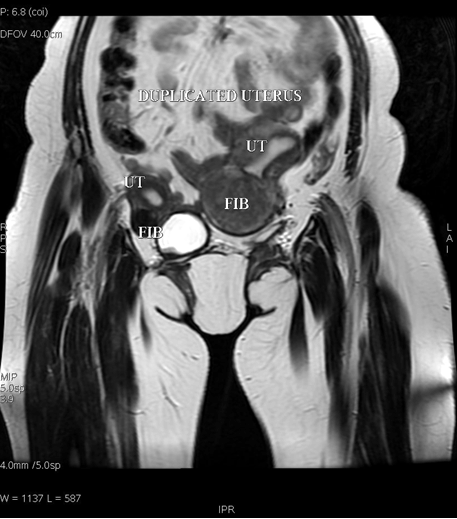

Figure 3: Magnetic resonance imaging scan showing showing the duplicated uterus with fibroids in both the uteri. Left uterus has larger fibroid. UT: Uterus, FIB: Fibroid.